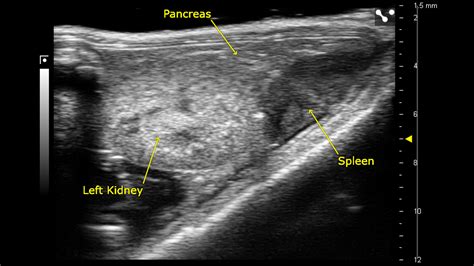

• Imaging Studies: Ultrasound, CT scan, or MRI can provide detailed images of the spleen and help diagnose conditions such as splenomegaly or splenic rupture.

• Imaging Studies: Ultrasound, CT scan, MRI, or endoscopic ultrasound can provide detailed images of the pancreas and help diagnose conditions such as pancreatic cancer or pancreatitis.

• spleen and pancreas anatomy

• spleen and pancreas location